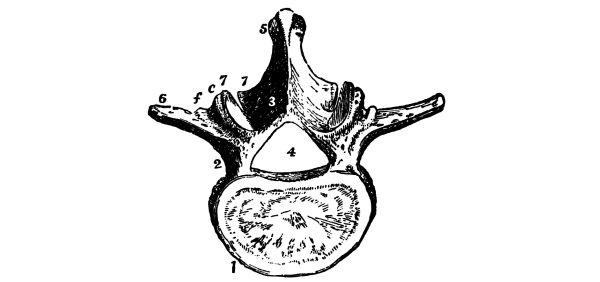

| The Back | 88 |

The Spine, 88—The Vertebræ, 88—Muscles of the Neck, 92—Muscles of the Back, 93. |

The Cerebrum, 75—The Cerebellum, 78—Pons Variolii, 78—Medulla Oblongata, 78—Spinal Cord, 79—Brain-centers, 81—Motor Tract, 82—Sensory Tract, 82—Reflex Action, 83—Cranial Nerves, 83—Spinal Nerves, 84—Brachial Plexus, 85—Sacral Plexus, 85—The Sympathetic System, 87—The Sympathetic Nerves, 87. |